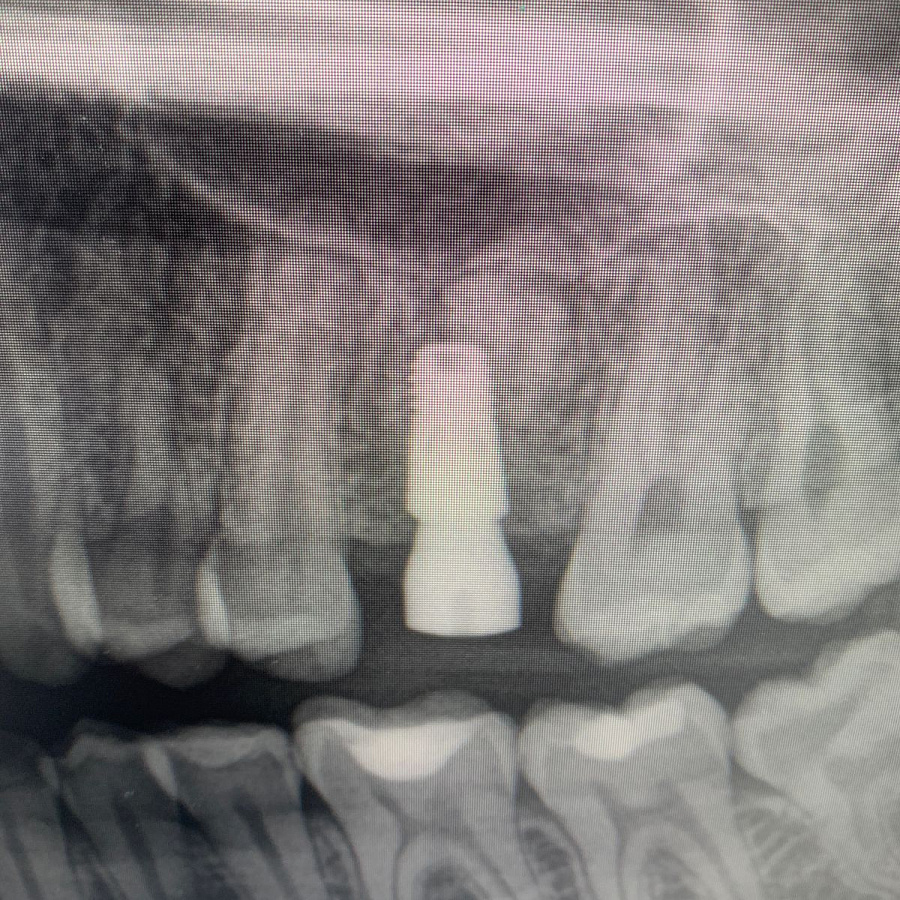

В ходе эндодонтической диагностики доктор обнаружил трещину в корне зуба.

Сохранить или вылечить зуб невозможно, поэтому было рекомендовано удаление зуба с последующей имплантацией.

После удаления таких зубов и извлечения кисты, в кости остаётся большой дефект. Поэтому сделать одномоментную имплантацию зуба, т.е. удаление и имплантацию за один приём невозможно. В таких случаях необходимы дополнительные хирургические манипуляции по подсадке искусственной кости, чтобы сохранить объём костной ткани для последующего протезирования.

Через 6 месяцев после подсадки кости - контрольный снимок и установка зубного имплантата.